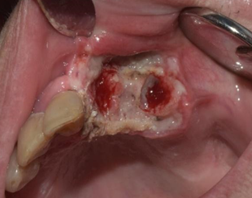

The patient was asked to come to the following appointment with a histopathological report of the nephrectomy performed and to coordinate the incisional biopsy of the oral lesion for the following week. The lesion had increased in size significantly by the second appointment (figures 4 and 5). The histopathological result of the nephrectomy performed was clear cell renal carcinoma.

Lesion evolution one week after evaluation, in the second appointment

A different strategy was used during the incisional biopsy: the clinician decided to remove the entire clinically visible lesion to control intraoperative bleeding and achieve proper hemostasis. Teeth 2.1 and 2.3 were extracted to help hemostasis. (figures 6 and 7).